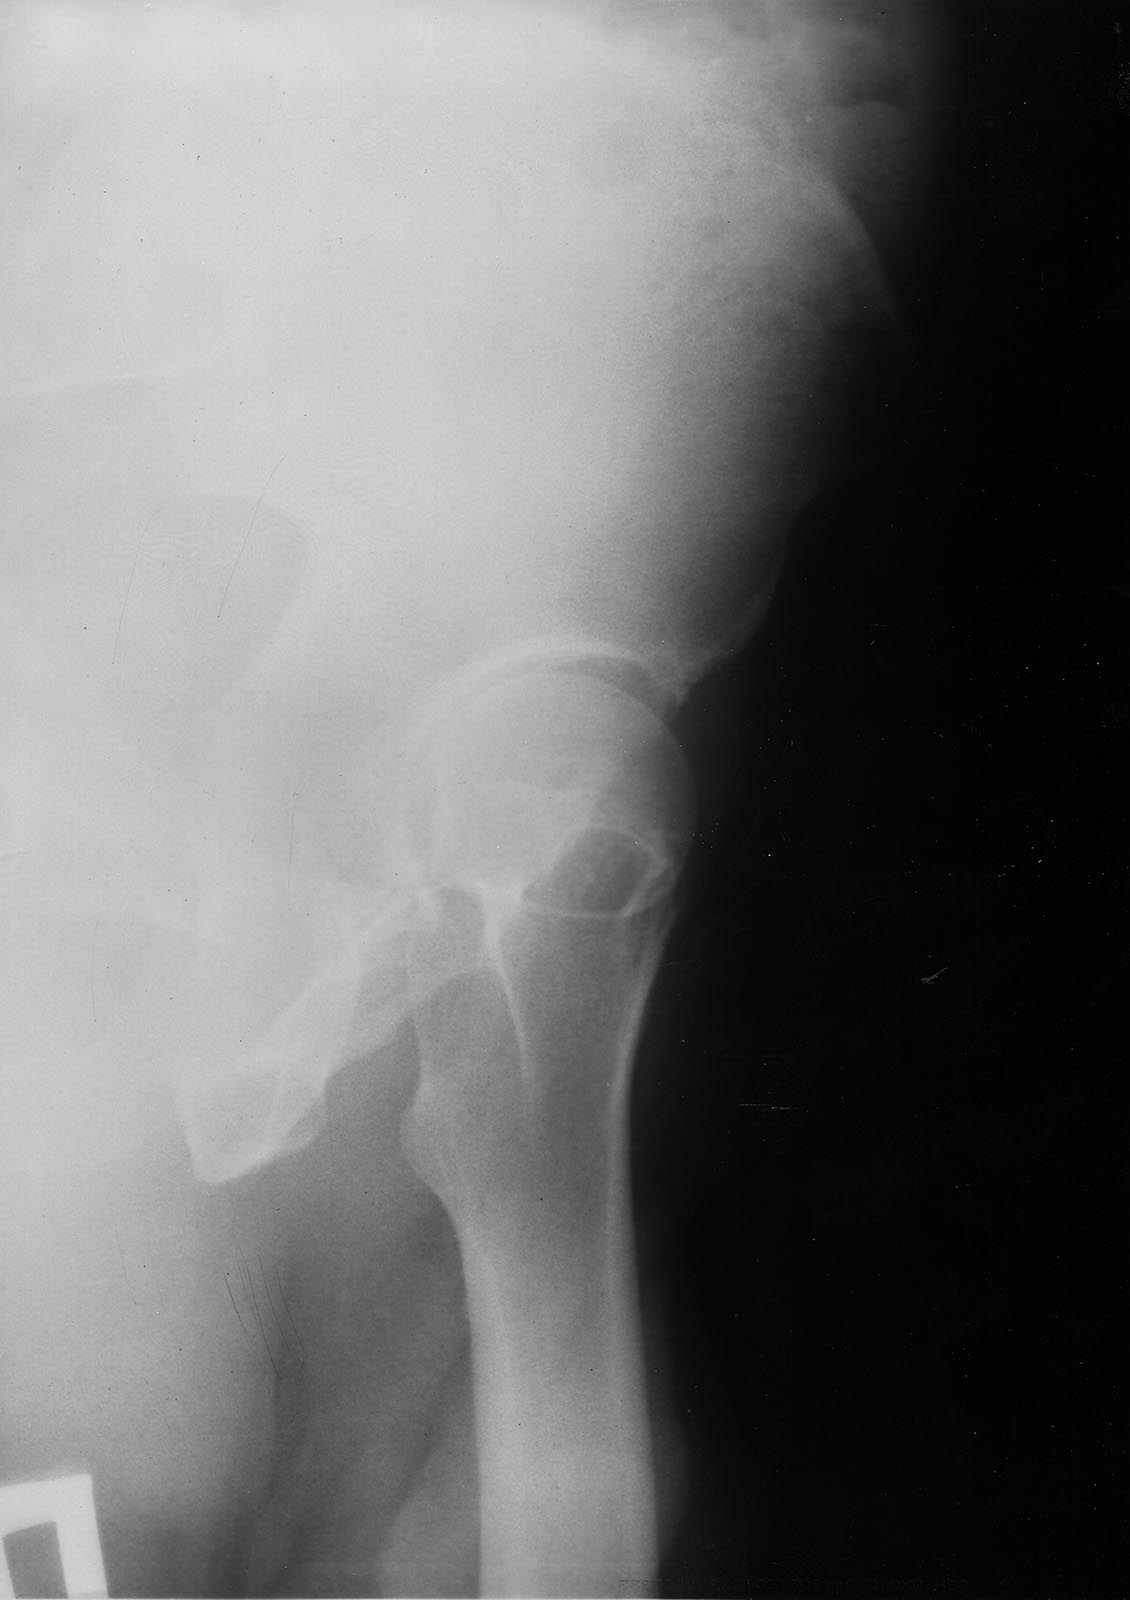

false profile